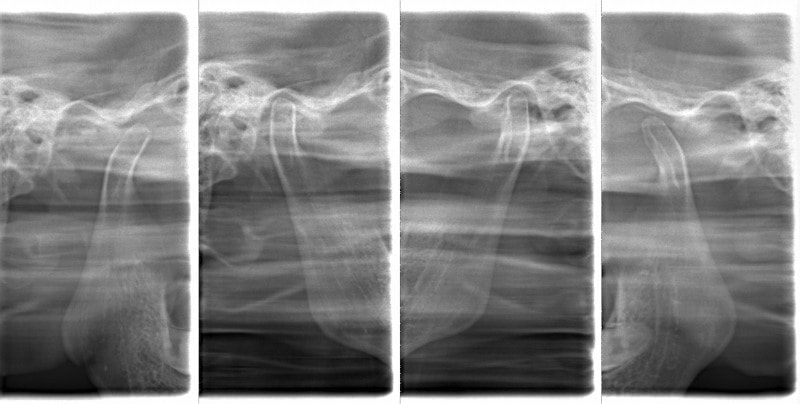

顎関節レントゲン分析

反対咬合の方はやはり下顎肢が細い傾向にあります。

顎位は良好な状態です。